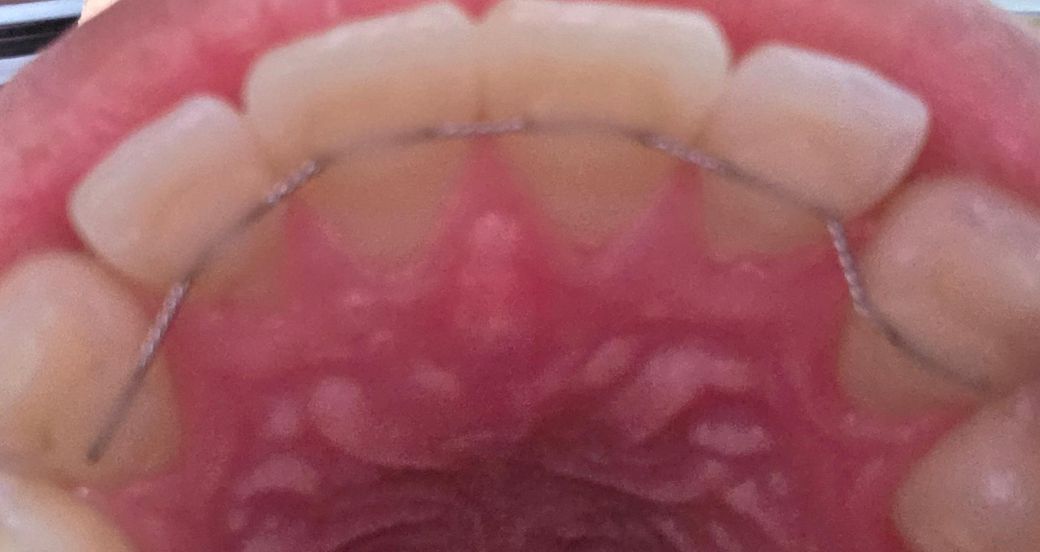

고정식 치아 교정장치 형태정상인가요?

오른쪽이 왼쪽이랑은 철사가 휘어진것처럼 다른데 시간이 오래되면서 변형이 된건지 아니면 원래부터 치아에 맞게 차이가 있었던건지 모르겠네요

고정식 유지장치가 원래 그렇게 부착되어 있었을 것으로 예상됩니다. 특별히 문제는 안보입니다.

사진상으로 보면 유지장치에는 문제가 없는거 같습니다. 변형이 된건 없으니 너무 걱정하지마세요.

현재 사진만으로는 정확한 판단이 어렵습니다. 말씀하신 FR(Fixed retainer)의 경우에는 환자의 치아 모양에 맞게 제작하게 됩니다. 만약 해당 철사가 갑자기 구부려지거나 맞지 않다면 치아에 힘이 가해져 치통이 발생할 수 있습니다. 단순 사진으로 모양이 변한 것 이외에 통증이나 불편감이 있는지 우선 체크해야 합니다. 그렇지 않다면 현재 사진으로 봐서는 크게 문제가 되는 부위는 보이지 않습니다.

설측교정 중 입니다. 철사 방향이나 각도는 치아의 위치에 따라 조금씩 다르게 나옵니다. 사진에서 보이는 것 정상적인 것입니다.

치아 표현 모양에 맞춰 굴곡이 있는 것으로 보입니다 사진상으로 봤을때 장치에 문제는 없어보입니다